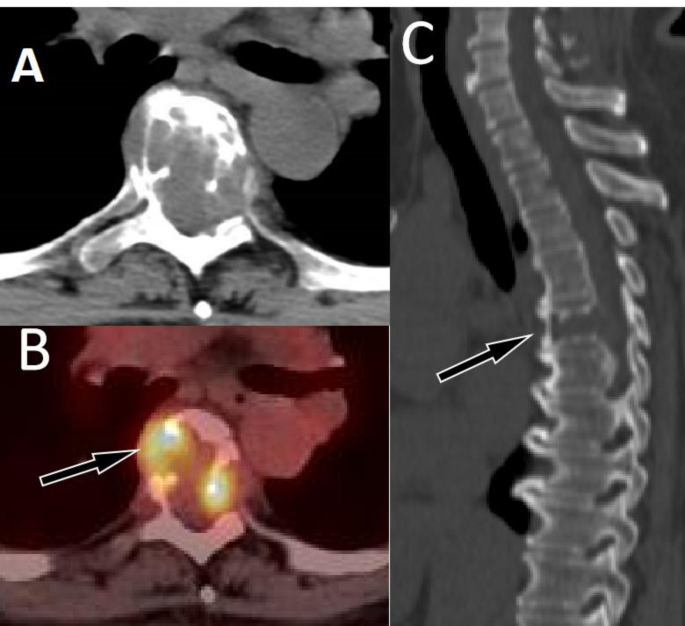

The current study included a total of 6 patients with epithelioid hemangioma, most of whom were located in the thoracic vertebrae, with the main lesion located in the vertebral body, but involving the vertebral plate or/and pedicle. In this group, all lesions presented eccentric osteolytic destruction without sclerotic edges, and the lesions broke through the bone cortex and formed soft tissue mass. Moreover, residual bone trabeculae can be seen within the lesion, and most vertebral bodies show compressive changes. On PET, obviously increased 18F-FDG uptake by lesions was observed (Fig. 5A-C).

A 51-year-old woman with EHE; (A) Axial CT revealed low-density osteolytic bone destruction shadow in the 6th thoracic vertebral body (arrow), which broke through the bone cortex and formed a soft tissue mass in the surrounding area; (B) The PET/CT fusion image of the corresponding area shows mildly increased 18F-FDG uptake (arrow), with a SUVmax of 6.0; (C) Sagittal CT reveals compressive changes in the vertebral body, with low-density cavity changes in the neutral state of the vertebral body (arrow), without sclerotic rims.